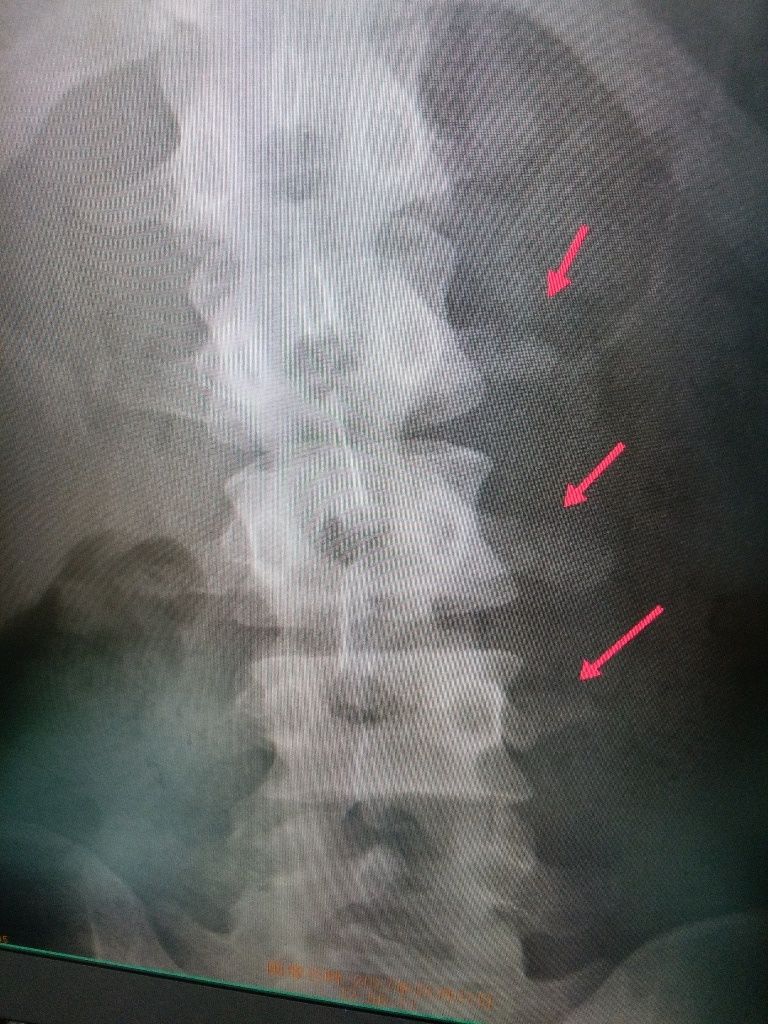

オーストラリア戦で転倒して

左鎖骨骨折と腰の横突起骨折してしまい 一時 帰国

イメージ 1

手術後 14日でタイ戦に参戦のため成田空港から旅立ちました

ドクターストップとしましたが チームと本人の強い希望で参戦です

イメージ 2

なんと世界で6位を 獲得しました!

結果オーライでしたが リスクもありました。

日本を背負うトップライダーの強い気持ちを感じます